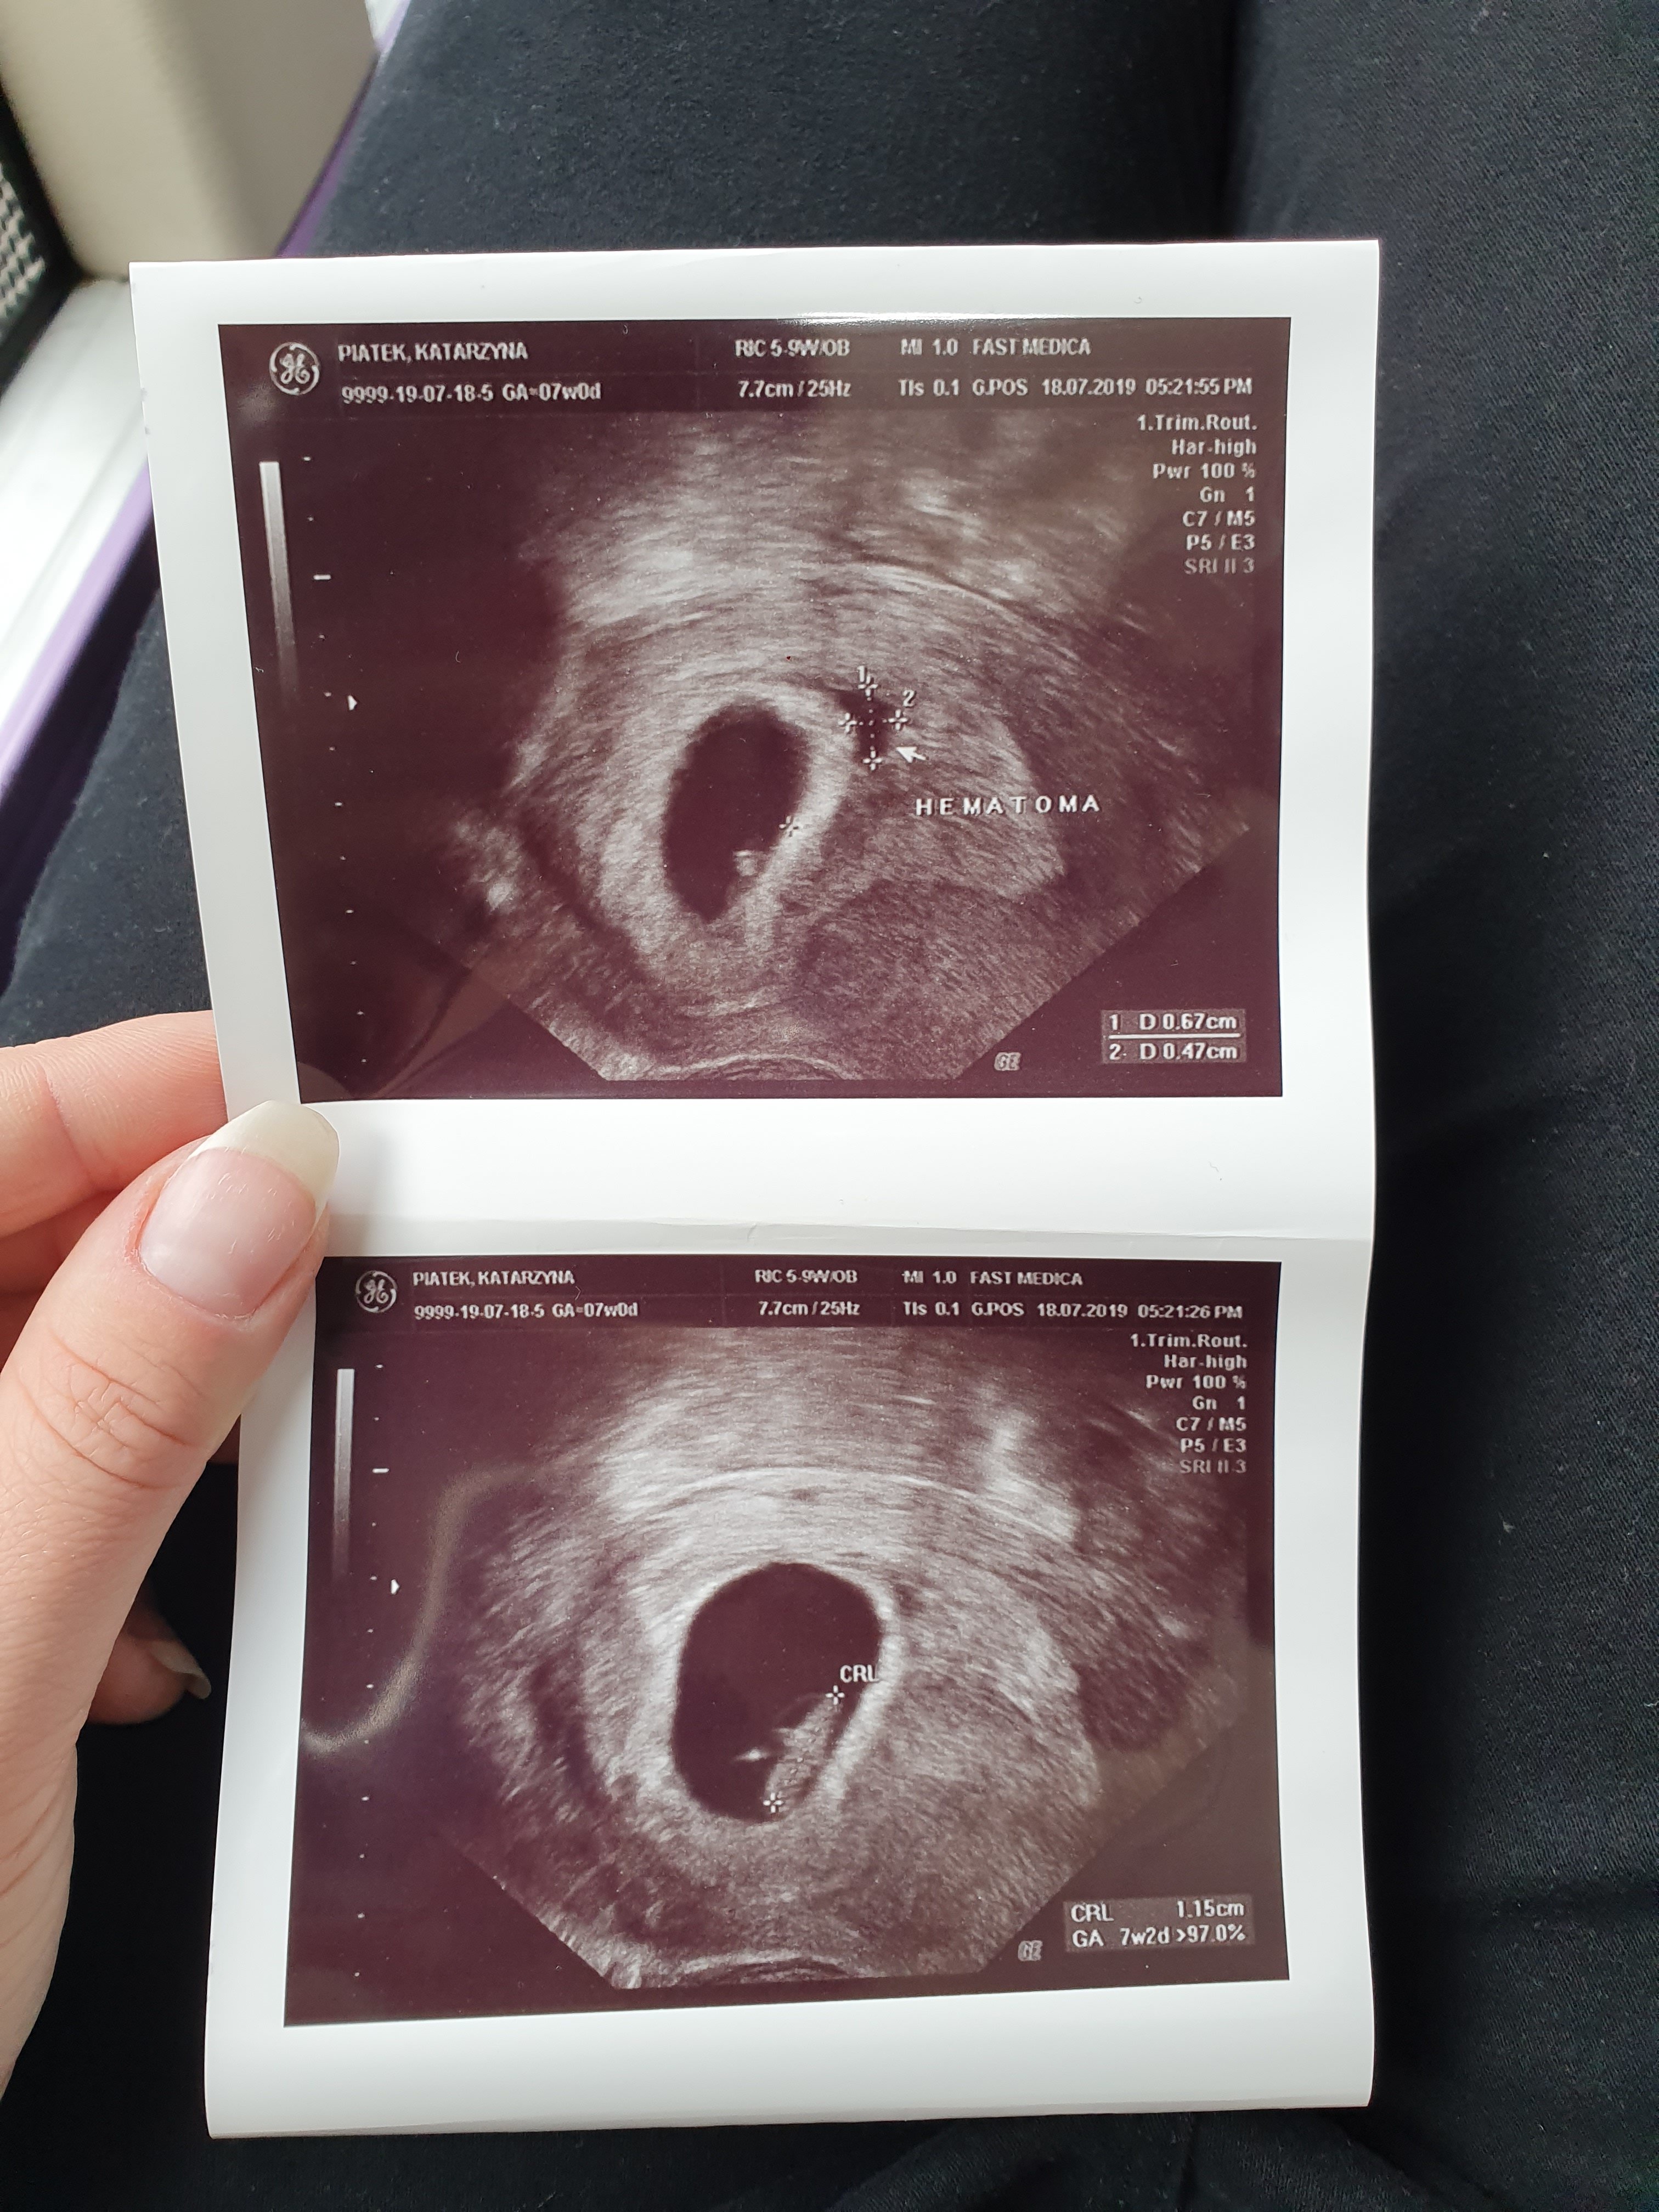

Hej dziewczyny ja byłam wczoraj na wizycie.

Nie miałam plamien ani razu ale dostałam progesteron na miesiąc oraz zakaz seksu

Powiedział że jest krwiak który jakby miał zrobić coś groźnego to już by zrobił ale.lepiej niech się szybko wsiaknie.

Ciaza rozwija się prawidłowo serduszko bije prawidłowo

Wiek ciazy 7t2d

Termin na 3.03

Cieszę się bardzo ❤